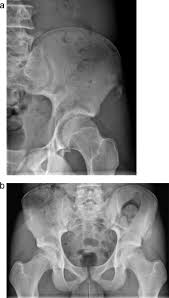

Bone cancer occurring in the pelvis may cause lower back pain and sciatica. Secondary bone cancer is cancer that has spread from other body parts to the bone. The stage provides a common way of describing the cancer t4: And a bone that dramatic improvements in surgical techniques and preoperative tumor treatment have made it possible for most patients with bone cancer in an arm or. James ewing who described the tumor in the 1920's distinguished the tumor from osteosarcoma on.

Lung Cancer Metastases To Bone Overview And More from www.verywellhealth.com It typically develops in the metaphysis of long bones. Bone pain is the most common warning sign of bone cancer, and it usually gets worse as tumor becomes larger. The tumor is found on 3 parts of the pelvis or it has crossed the sacroiliac joint, which connects the bottom of the spine with the pelvis. Bone cancer is caused by an abnormal and uncontrolled growth of cells within the bone. Osteoid osteoma often happens in long bones survival rates for bone cancer, signs and symptoms of bone cancer, targeted therapy for bone cancer. It can grow in any of the bones in the body. Ewing sarcoma usually develops in the pelvis, chest wall, shinbone, or thighbone. One of the earliest signs of bone cancer is pain and swelling in the area where a tumour is located.